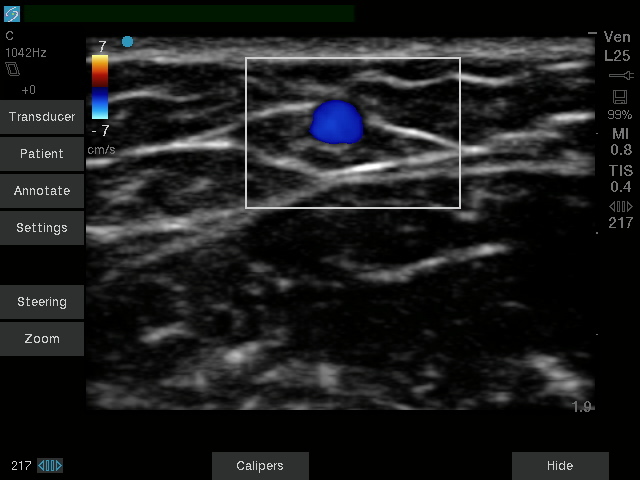

Vasküler Erişim için Sonosite SII-VA, hat yerleştirmeleri sırasında kullanım kolaylığı ve güvenilirliği nedeniyle klinisyenler için ideal bir araçtır. Basitleştirilmiş, dayanıklı ve uygun fiyatlı olan bu sistem, birincil bir amaç için yaratılmıştır: Ultrason rehberliğinin yardımıyla Merkezi hatlar, PICC’ler ve Periferik IV’ler gibi vasküler erişim prosedürlerinin başarı oranlarını iyileştirmenize yardımcı olmak.

Daha iyi görüş, daha derin anlayış. Sonosite, klinisyenlerin en zorlu ihtiyaçlarını karşılamak için yeni bir görüntü performansı standardını yeniden tanımlıyor.

| Doğrusal | 13-6 MHz | 6 cm | Arteriyel, Venöz |